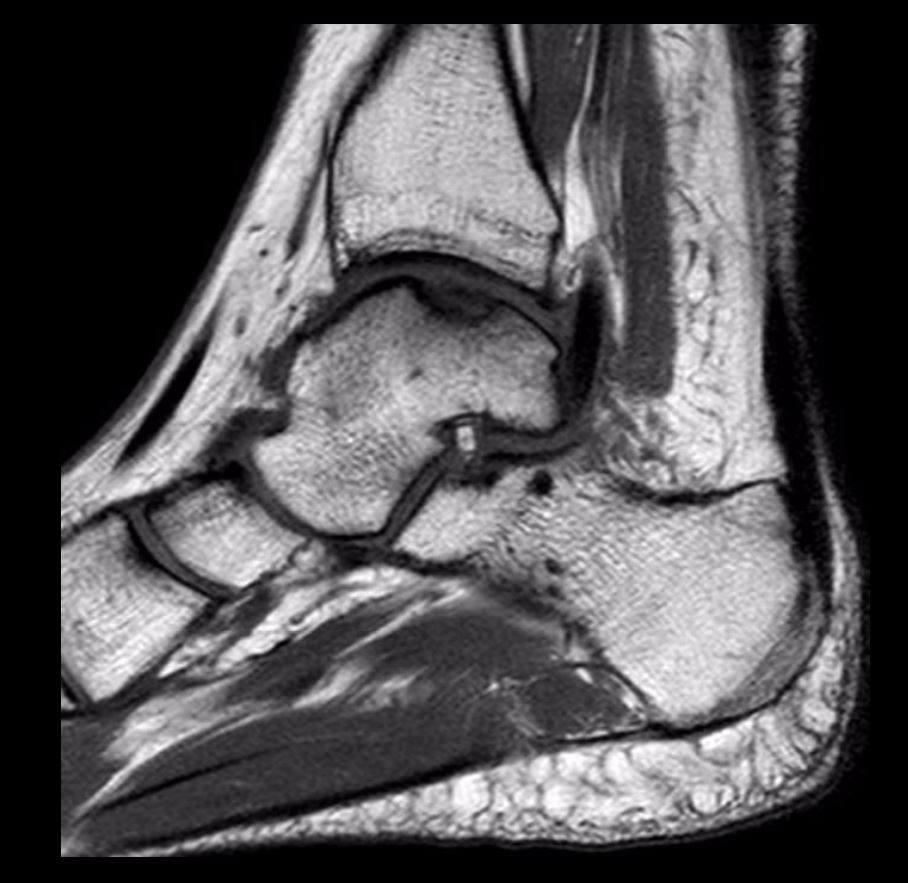

Difetto cartilagineo o difetto ostocondrale

Si tratta di aree localizzate con cartilagine e osso subcondrale (la porzione ossea al di sotto della cartilagine) danneggiate nell'articolazione della caviglia. I difetti osteocondrali sono di solito causati da lesioni alla caviglia, quali fratture e distorsioni. I sintomi più comuni includono dolore alla caviglia e gonfiore. I pazienti spesso lamentano blocchi e scricchiolii nella caviglia. La diagnosi viene realizzata utilizzando radiografie e risonanza magnetica. La TAC può essere utilizzata per valutare meglio eventuali lesioni che si approfondiscono nella porzione ossea. Il trattamento si basa sulla dimensione, posizione e stabilità del difetto osteocondrale. Solitamente la chirurgia consiste nell’asportazione della cartilagine danneggiata e nelle microperforazioni dell'osso nella sede di lesione per favorire la guarigione. Negli ultimi anni, si sono sviluppati substrati cartilaginei e scaffold artificiali che permettono la ricolonizzazione della cartilagine nella sede della lesione, dopo la sua bonifica.